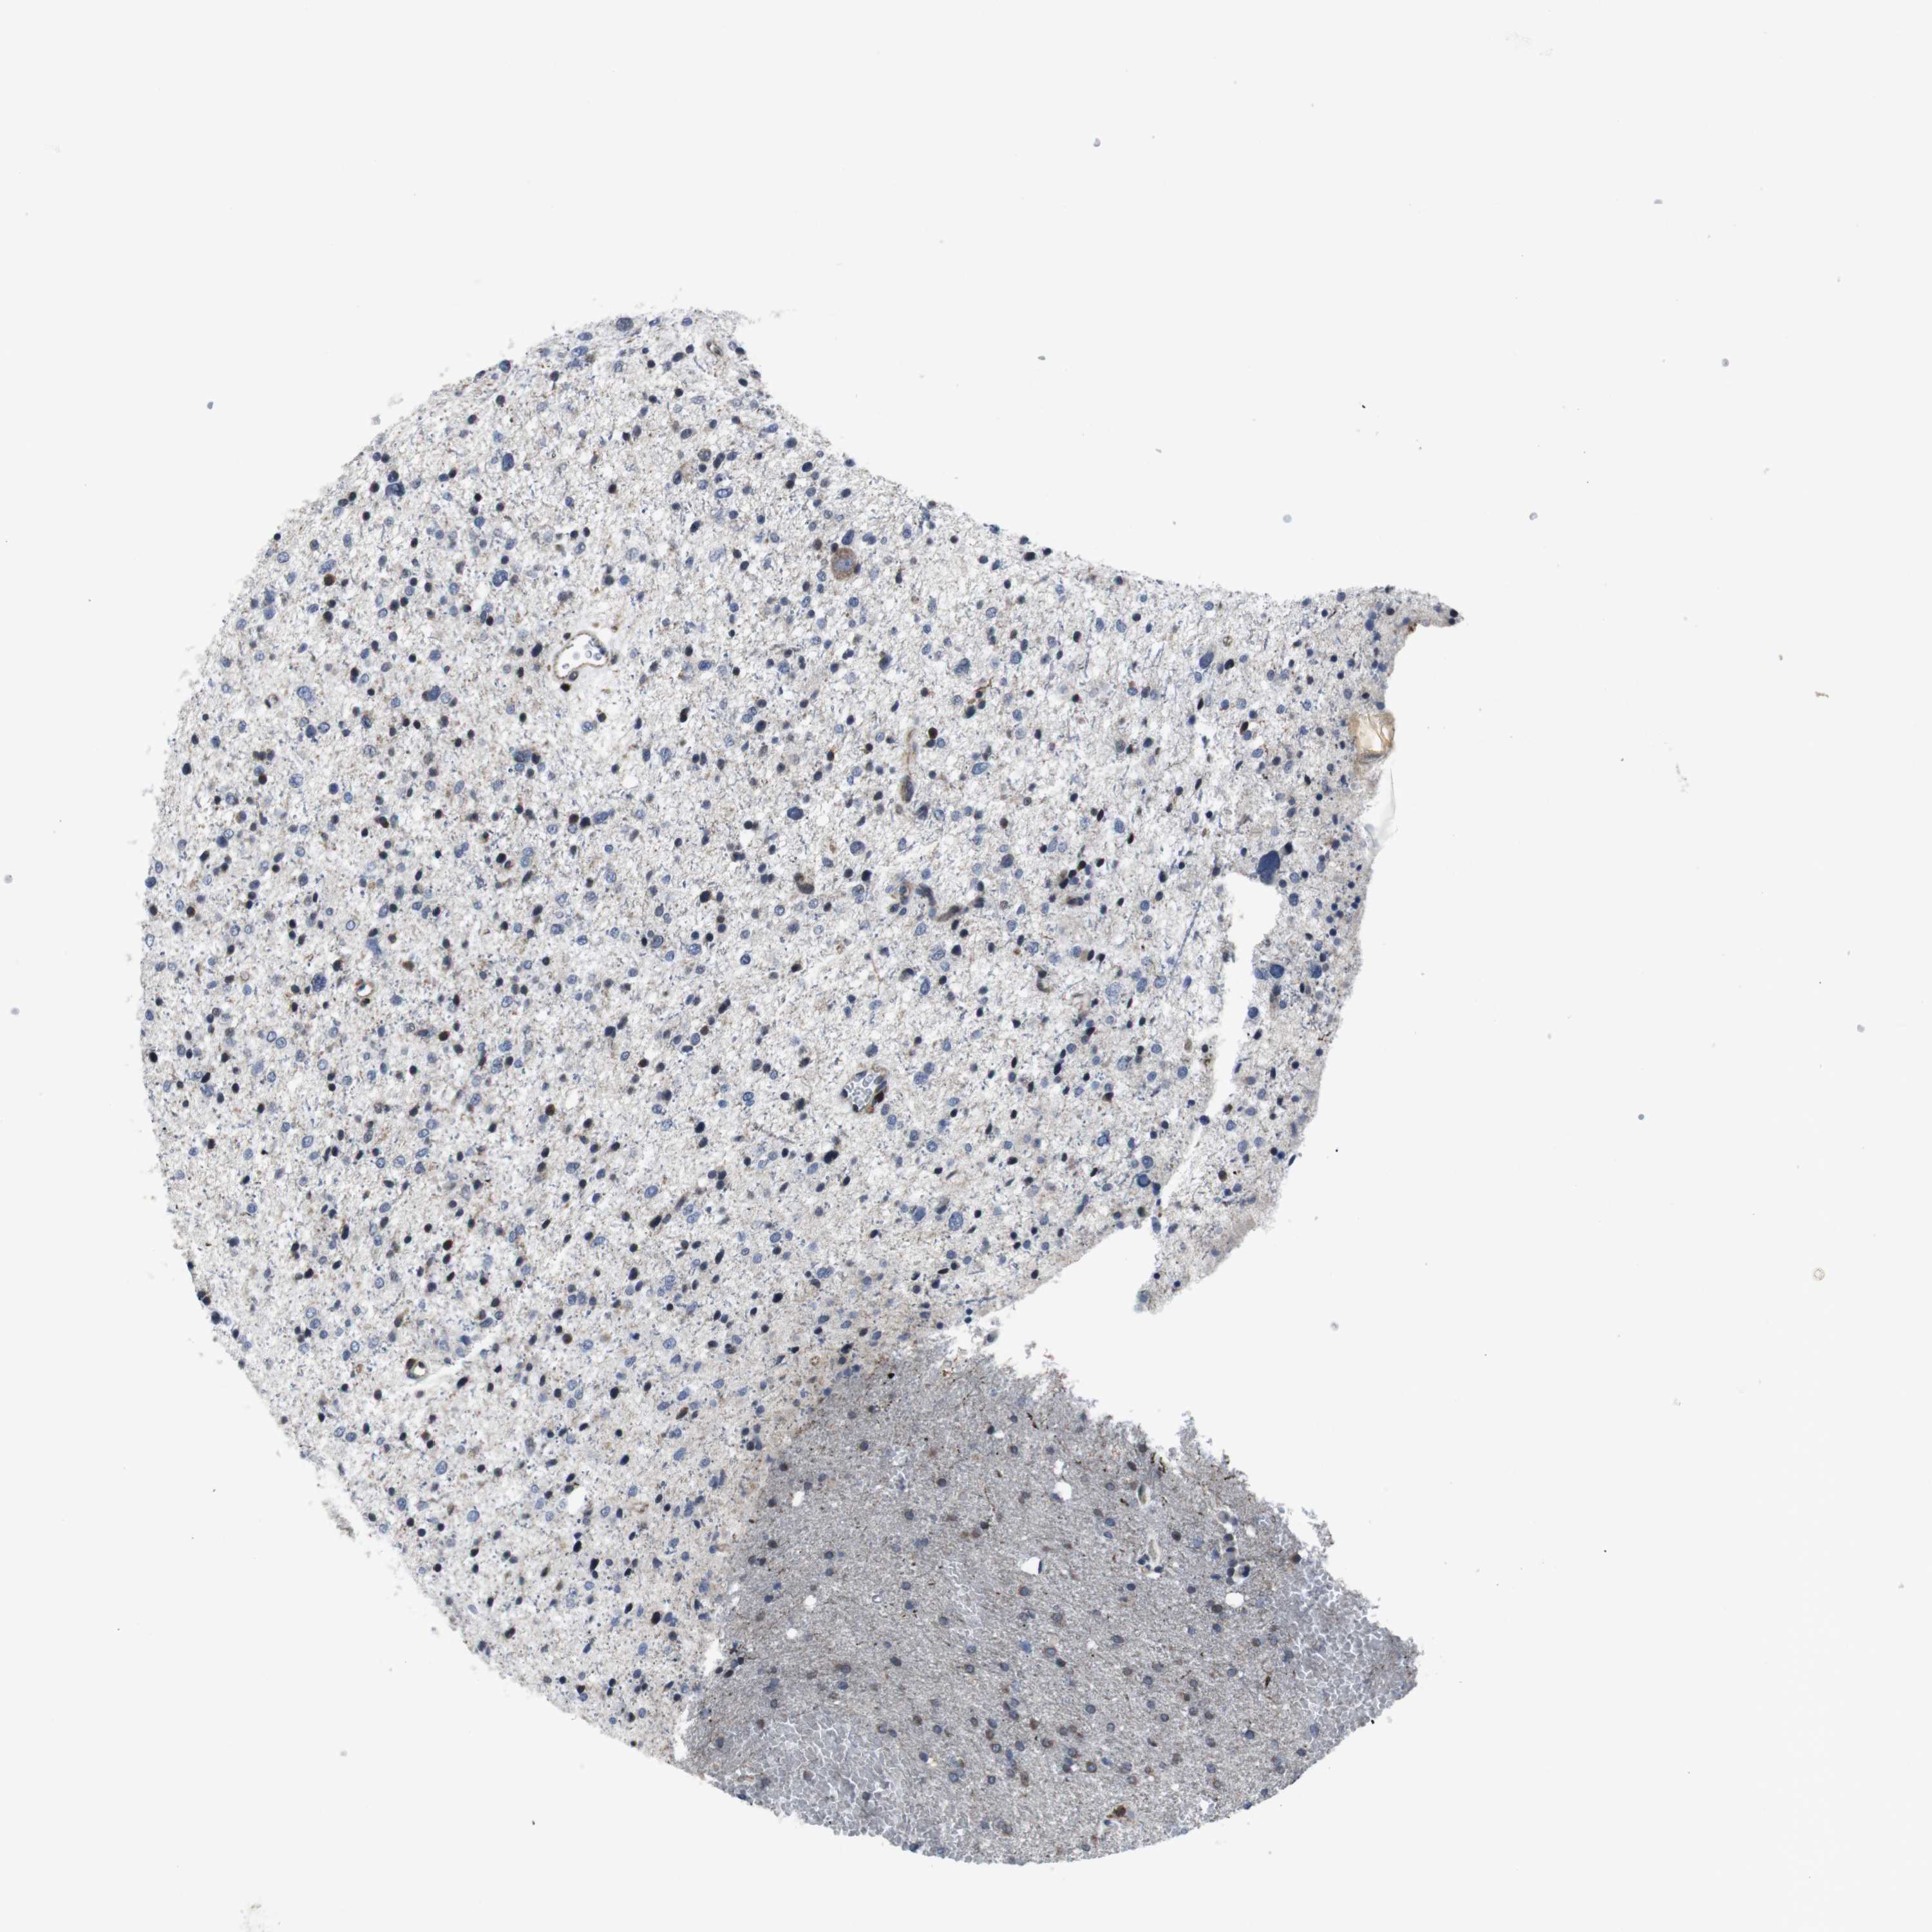

GLIOMA - Protein expressioni

A mouse-over function shows sample information and annotation data. Click on an image to view it in a full screen mode. Samples can be filtered based on level of antibody staining by selecting one or several of the following categories: high, medium, low and not detected. The assay and annotation is described here.

Note that samples used for immunohistochemistry by the Human Protein Atlas do not correspond to samples in the TCGA dataset.

Antibody stainingi

Antibody staining in the annotated cell types in the current human tissue is reported as not detected, low, medium, or high, based on conventional immunohistochemistry profiling in selected tissues. This score is based on the combination of the staining intensity and fraction of stained cells.

Each image is clickable and will lead to virtual microscopy that enables deeper exploration of all samples and also displays staining intensity scores, fraction scores and subcellular localization as well as patient and tissue information for each sample.

Antibody HPA001860

Antibody CAB013108

Staining

High

Medium

Low

Not detected

Intensity

Strong

Moderate

Weak

Negative

Quantity

>75%

75%-25%

<25%

None

Location

Nuclear

Cytoplasmic/membranous

Cytoplasmic/membranous,nuclear

Glioma, malignant, High grade

Glioma, malignant, Low grade